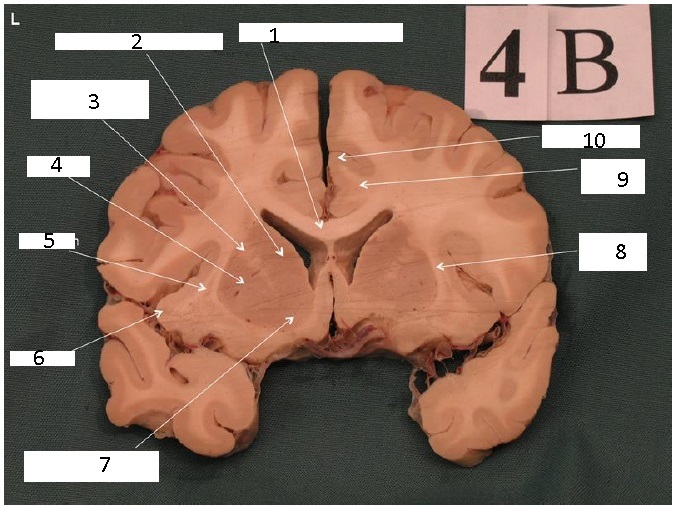

Identify 1

Head of Caudate Nucleus

Identify 2

Putamen

Body of Corpus Callosum

Cingulate Gyrus

Note: Cingulate gyrus + parahippocampal gyri = limbic system

Identify 3

Cingulum

Note: Part of the limbic lobe

Identify 4

Temporal Lobe